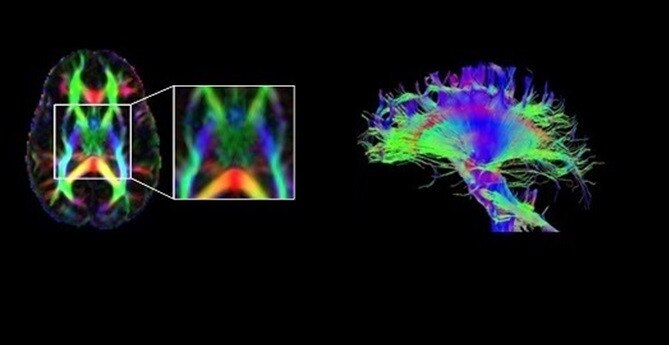

This one-stop solution enables you to imagine brain, spine, vascular and peripheral nerve anatomy with exceptional tissue contrast. These motion-insensitive techniques feature single-click auto alignment, providing the complete neuro solution from scanning to post processing.

NeuroWorks also includes Cube, our 3D volumetric imaging suite, standard with every system. This application allows you to suppress CSF and either white or gray matter to increase lesion conspicuity.